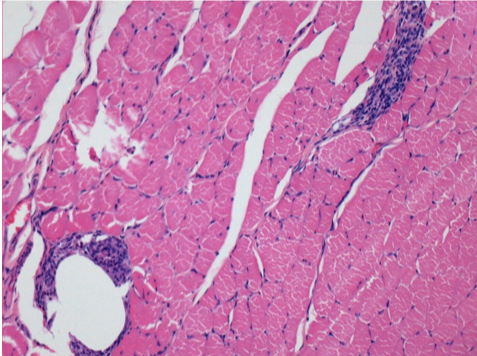

L:Pretibial-No treatment

10 days after Endopeel Injection 0.1ml in the right pretibial muscle.

Here you may see the formation of the vacuoles which are surrounded by lymphocytes. Vacuoles are different from tissue necrosis . The presence of lymphocytes is related to the permeability of the cell membranes.